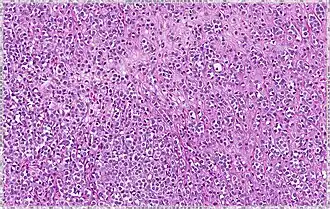

Histopathology of invasive lobular carcinoma (ILC), next to lobular carcinoma in situ (LCIS) -

Invasive lobular carcinoma demonstrating a predominantly lobular growth pattern -

Lobular breast cancer. Single file cells and cell nests. -

ILC may be subtle on low magnification (left). Higher magnification (right) shows invasive growth pattern and vesicular nuclei with prominent nucleoli.